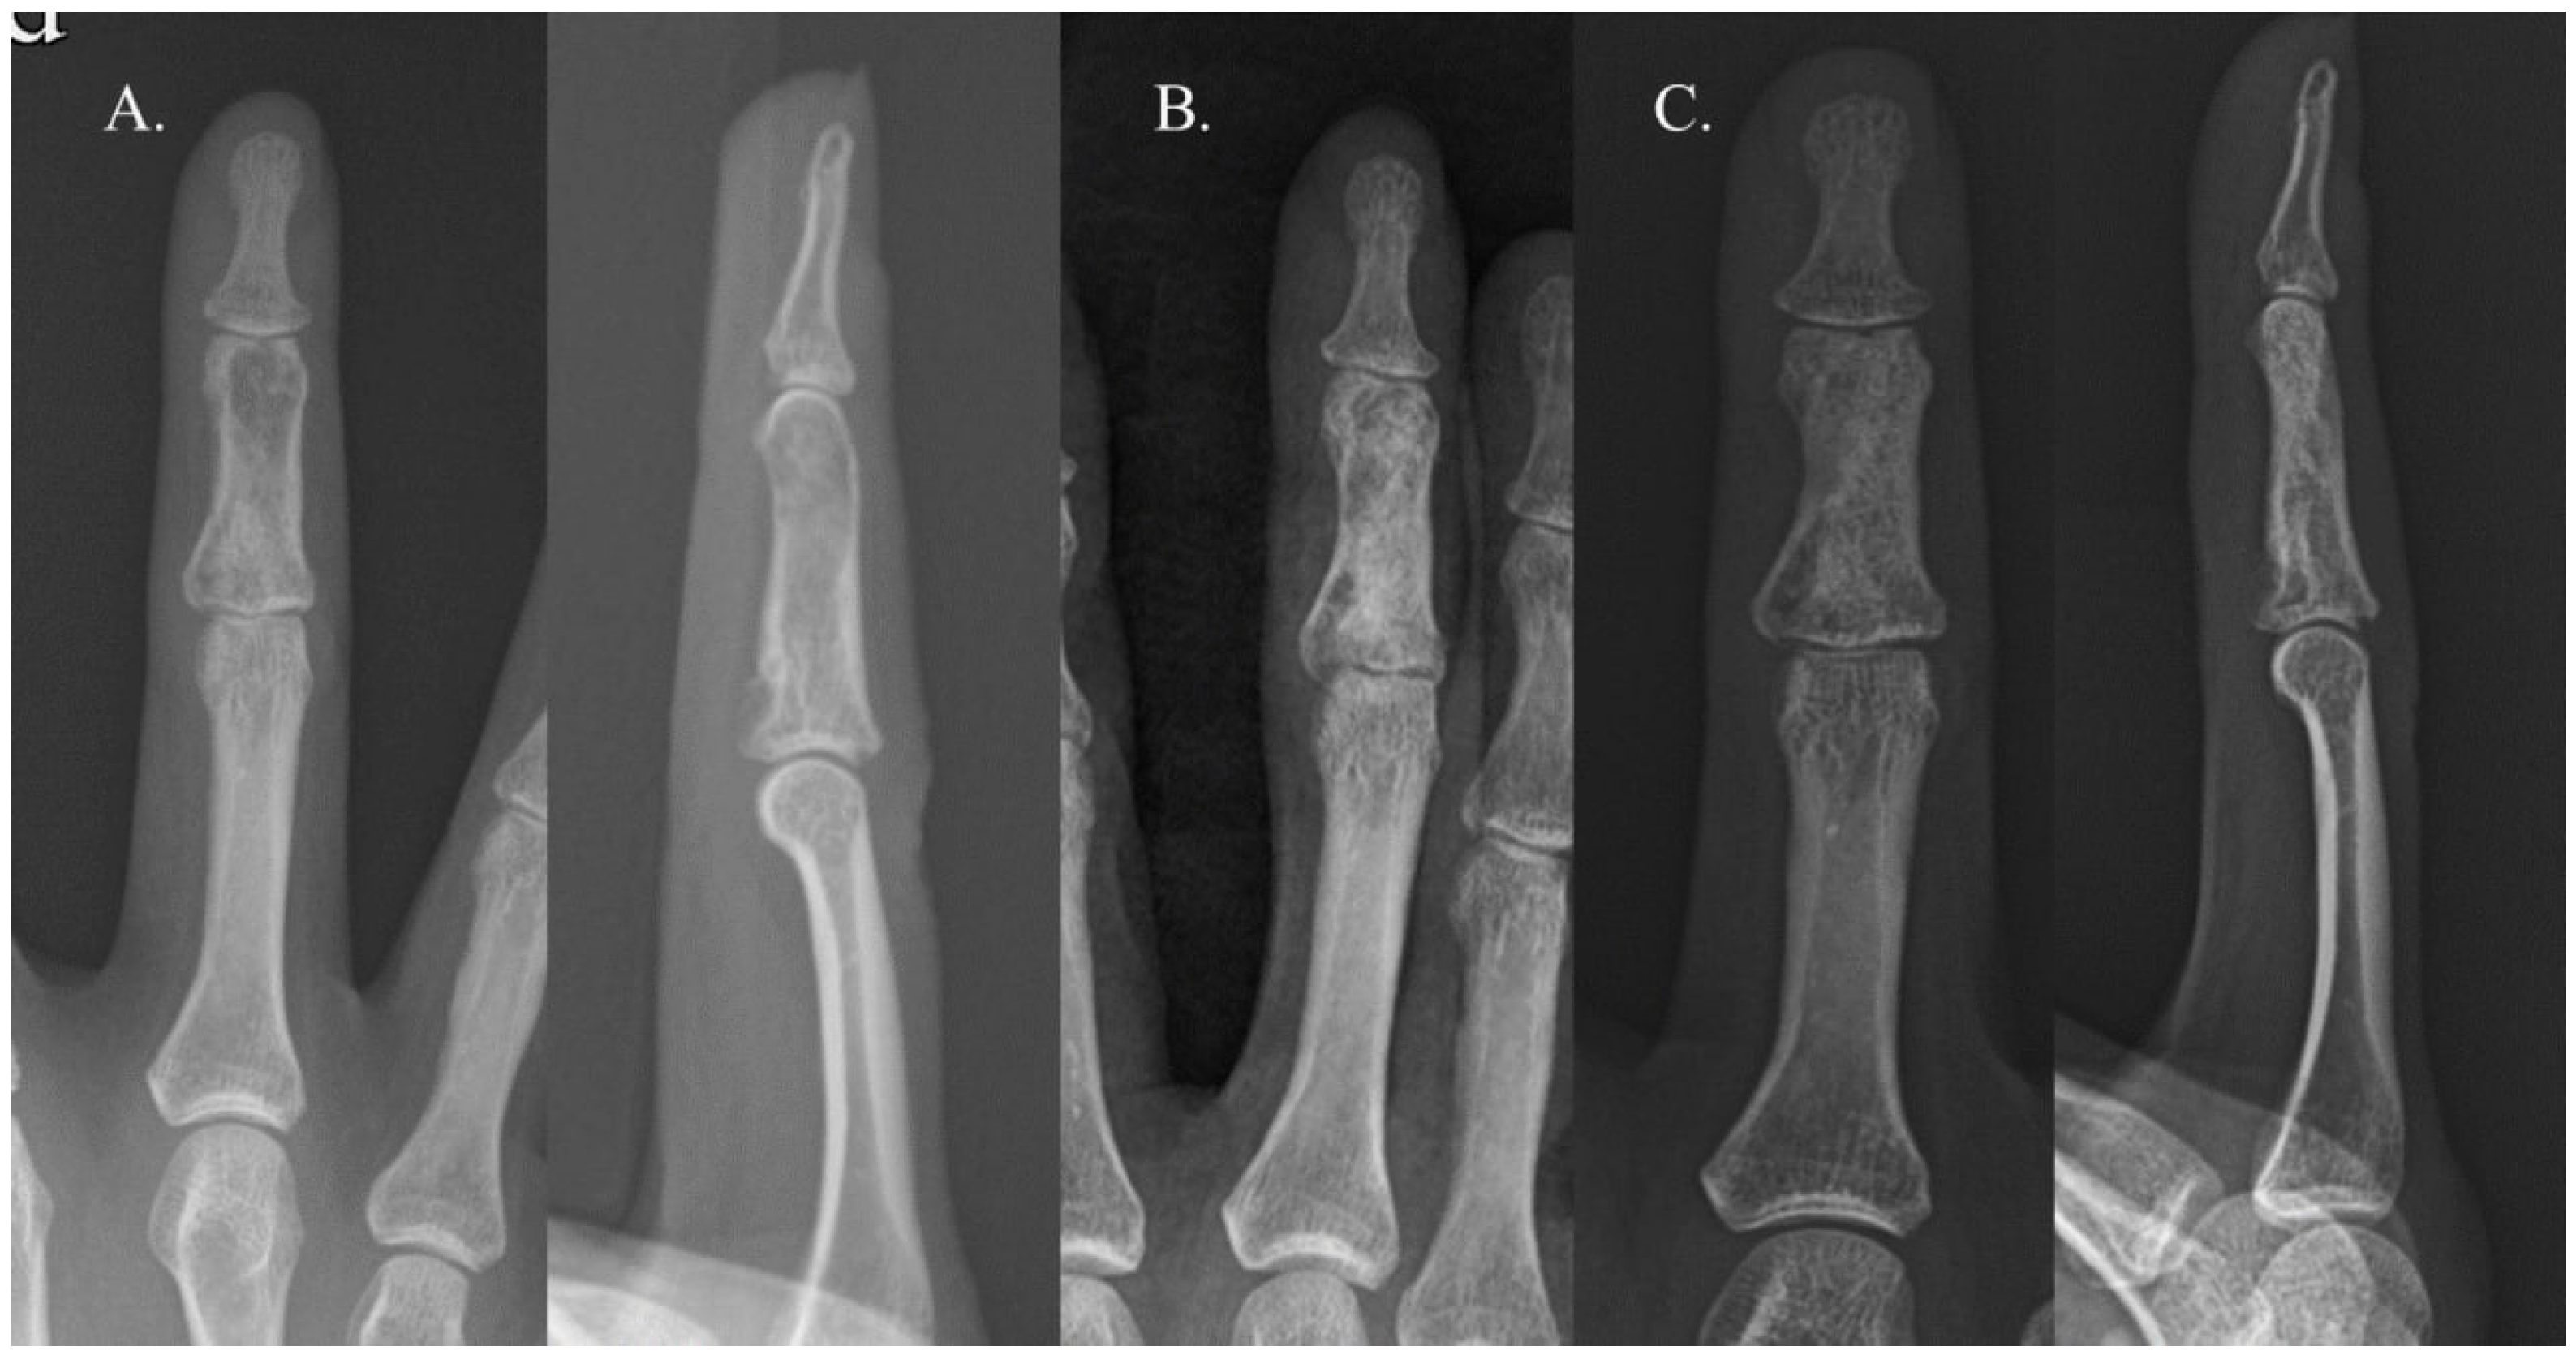

2.1. Surgical Procedure and Rehabilitation

2.2. Radiographic Evaluation